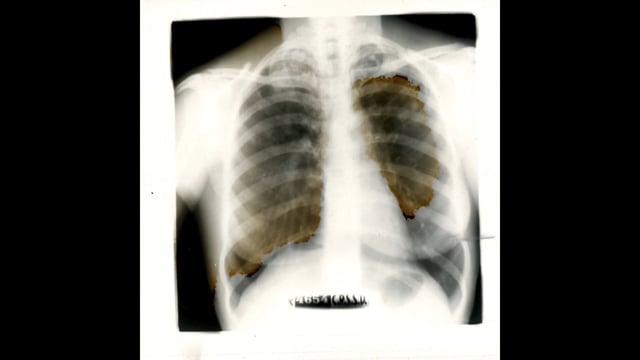

The east of France is dying, we see a half-empty factory and a mass of workers caught between precariousness and impotence. X-rays of their calcified lungs scroll by at the rhythm of a mechanical press under which one suffocates.

• Still 1